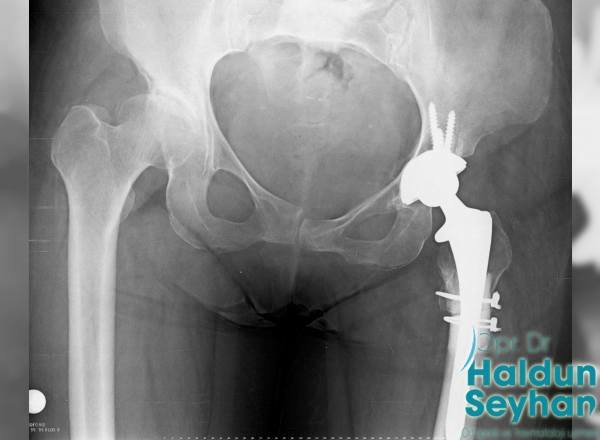

Kalça protezi, çeşitli sebeplerle bozulma yaşanmış eklem yüzeyine yerleştirilen, kobalt-krom veya titanyumdan oluşan ana parçalar olmak üzere, bu parçaların eklemleştiği yerde polietilen, metal ya da seramik parçalardan oluşmaktadır. …

Kalça protezi ameliyatı farklı şekillerde yapılabilir. Yaşı ilerleyen hastalarda kemik kalitesi düşük olabilir. Bu hastalara protez kemik çimentosu adı verilen bir dolgu maddesi yardımıyla işlem yapılabilir. …

Total kalça artroplastisi, eklemin yumuşak hareketini sağlamak için metal, seramik ve polietilenden yapılmış yıpranmış eklem yüzeylerini özel olarak tasarlanmış parçalarla kaplayarak yapay bir eklem oluşturmak için tasarlanmıştır. …